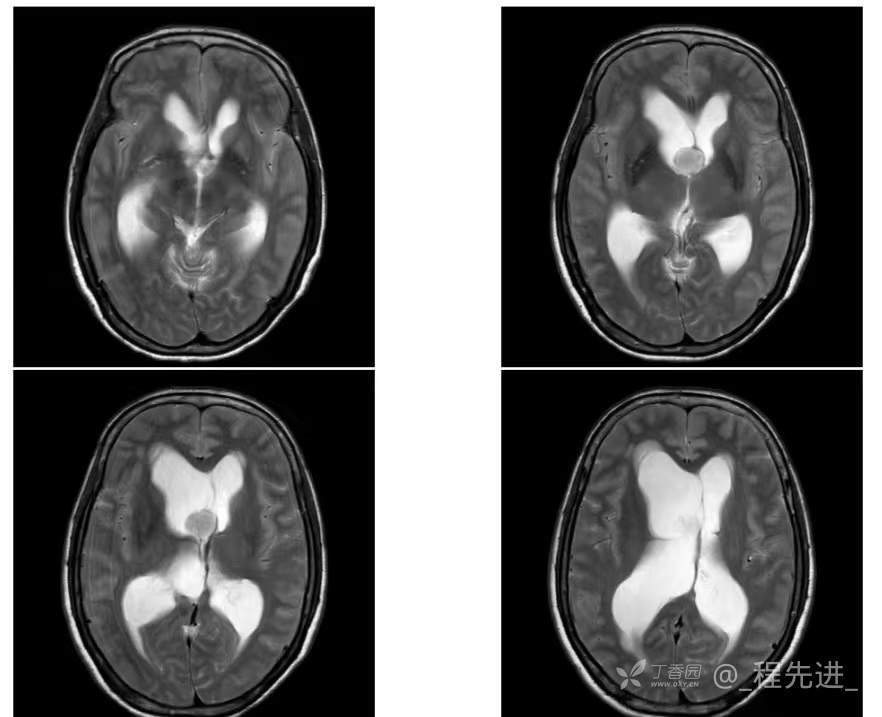

患者性别:女

患者年龄:55岁

简要病史:头痛头晕4年余,无明显诱因,10余年前因“输卵管破裂大出血”手术治疗

脑膜瘤 (78)

过渡型(混合性)脑膜瘤 (1)